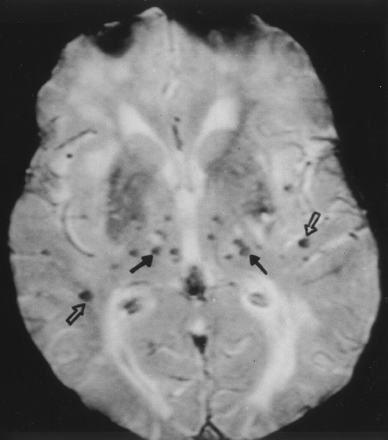

大脑在CADASIL microbleeds

Lesnik Oberstein et al。获得15个成员的t2加权MRI梯度回波荷兰CADASIL家庭确定脑microbleeds发生缺血性血管病变。Microbleeds CADASIL突变携带者症状出现在31%,暗示可能颅内出血的风险增加。

看到页面1066年